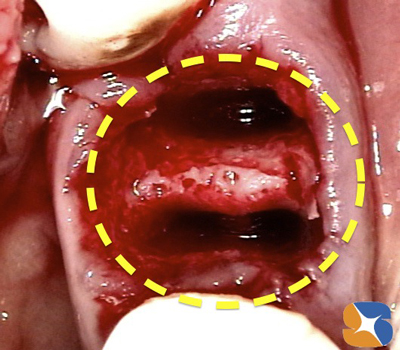

まずは、腐食した奥歯の抜歯を行いました。この場所に、骨を増殖させる治療を行いながらインプラントを埋めていきます。

動物由来ではない吸収性の骨の補填材…β-TCP(オリンパス社製)

AFGとCGF(自己血液由来のフィブリノーゲンの塊)

を使って抜歯した痕を全て隙き間なく、きっちり埋めます。